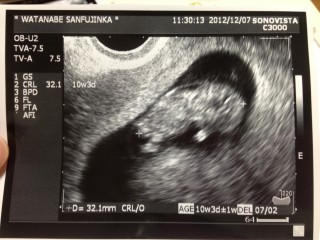

妊娠10週3日 / CRL=3.58cm / 心拍181

赤ちゃんは寝ていたようで、動いている姿は見られず。しかし心拍が高めなので、おきるかもしれないと先生。子宮を刺激したら、ちょっと起きた 手足パタパタこのころ頭部後ろにコブがないか超音波で確認するらしい。